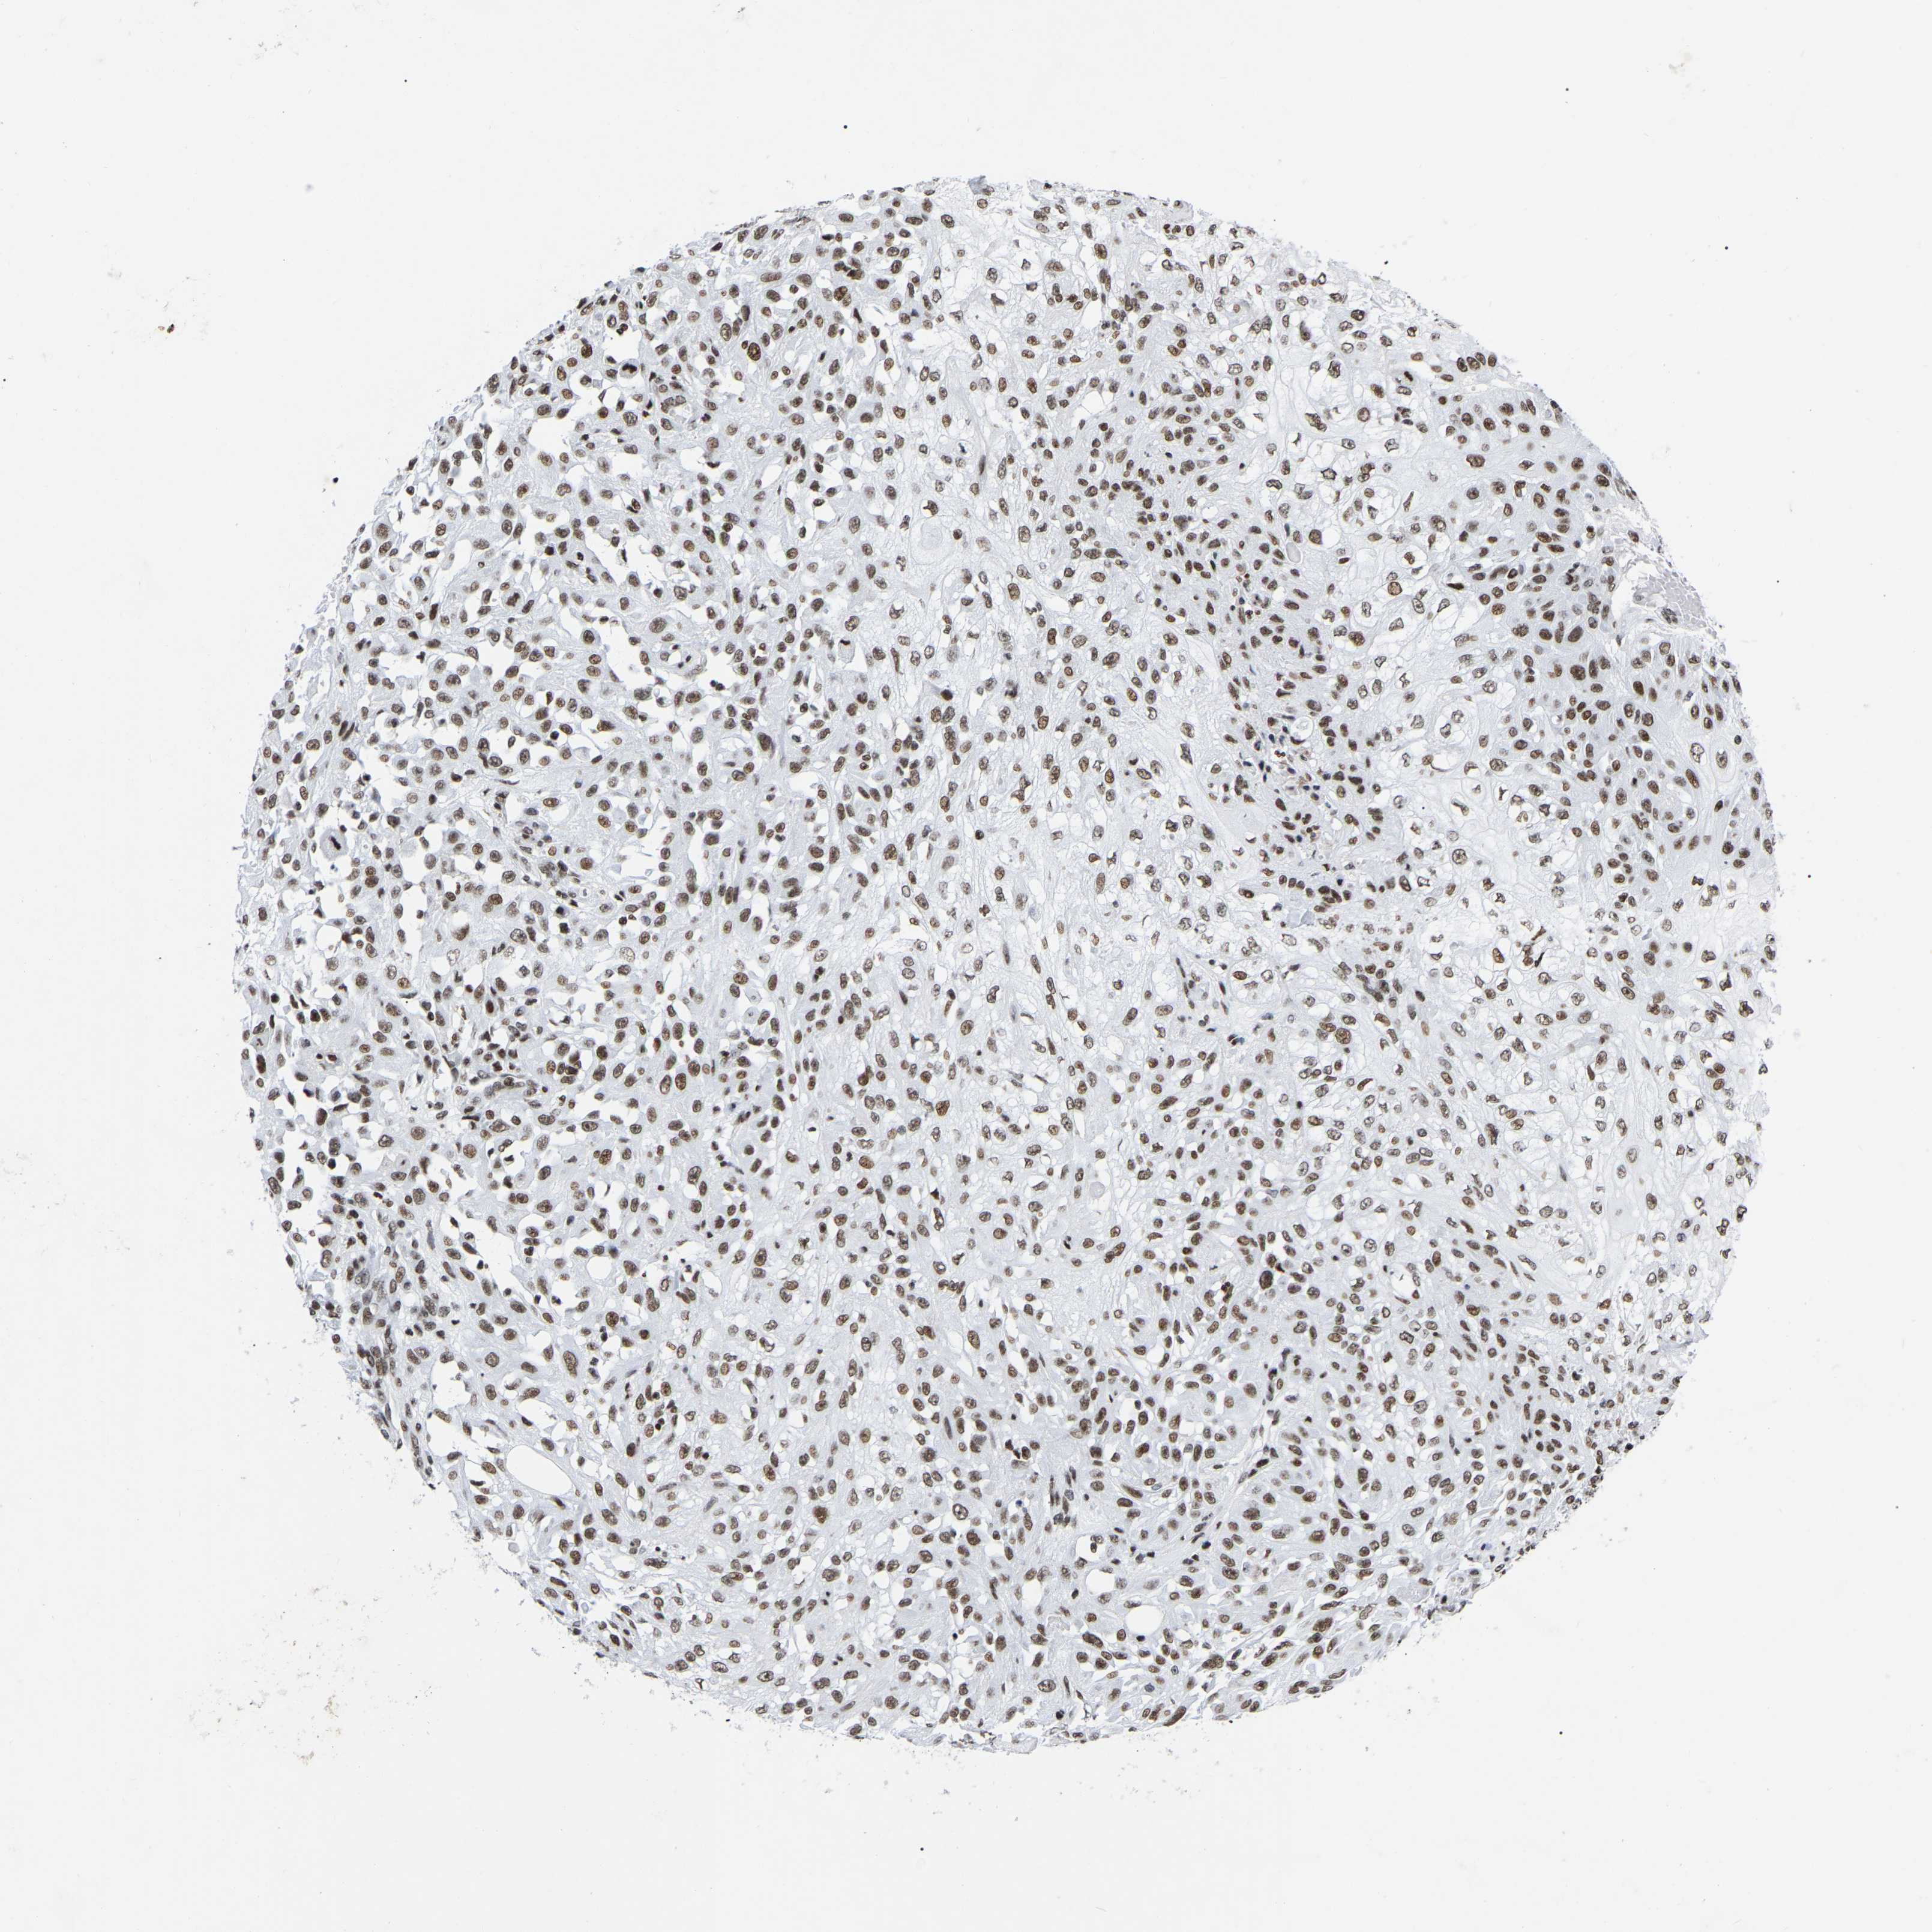

SKIN CANCER - Protein expressioni

A mouse-over function shows sample information and annotation data. Click on an image to view it in a full screen mode. Samples can be filtered based on level of antibody staining by selecting one or several of the following categories: high, medium, low and not detected. The assay and annotation is described here.

Antibody stainingi

Antibody staining in the annotated cell types in the current human tissue is reported as not detected, low, medium, or high, based on conventional immunohistochemistry profiling in selected tissues. This score is based on the combination of the staining intensity and fraction of stained cells.

Each image is clickable and will lead to virtual microscopy that enables deeper exploration of all samples and also displays staining intensity scores, fraction scores and subcellular localization as well as patient and tissue information for each sample.

Antibody HPA019463

Antibody HPA019481

Antibody CAB017151

Staining

High

Medium

Low

Not detected

Intensity

Strong

Moderate

Weak

Negative

Quantity

>75%

75%-25%

<25%

None

Location

Nuclear

Cytoplasmic/membranous

Cytoplasmic/membranous,nuclear

Squamous cell carcinoma, NOS

Squamous cell carcinoma, metastatic, NOS

Squamous cell carcinoma in situ, NOS